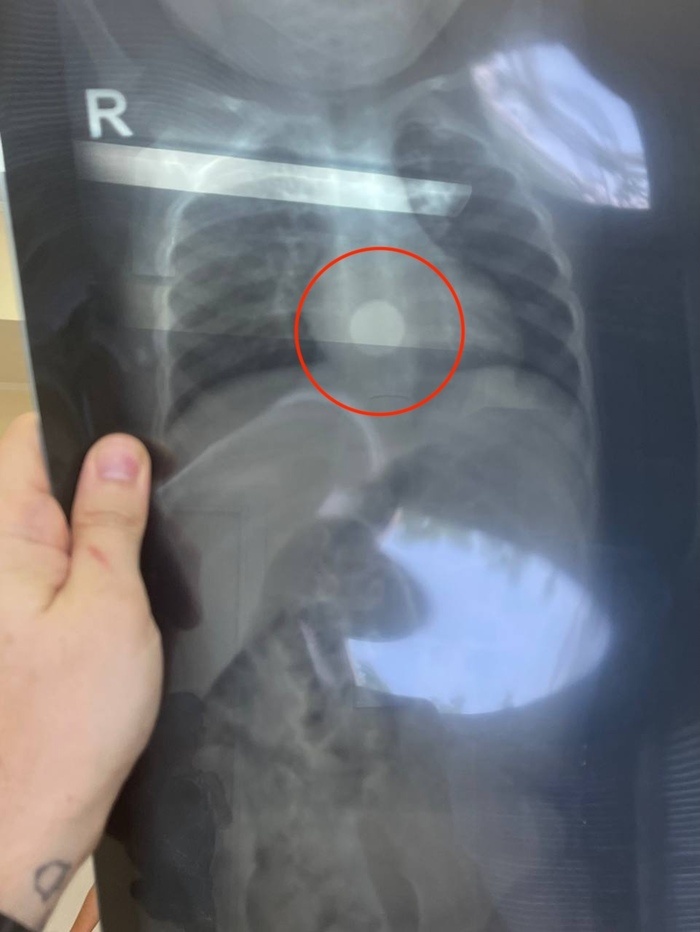

Вручает рентгенограмму грудной клетки ребёнка 1-2 лет. В нижней трети пищевода - металлическое инородное тело (!).

И удалил батарейку.

БАТАРЕЙКУ. (!!!!)